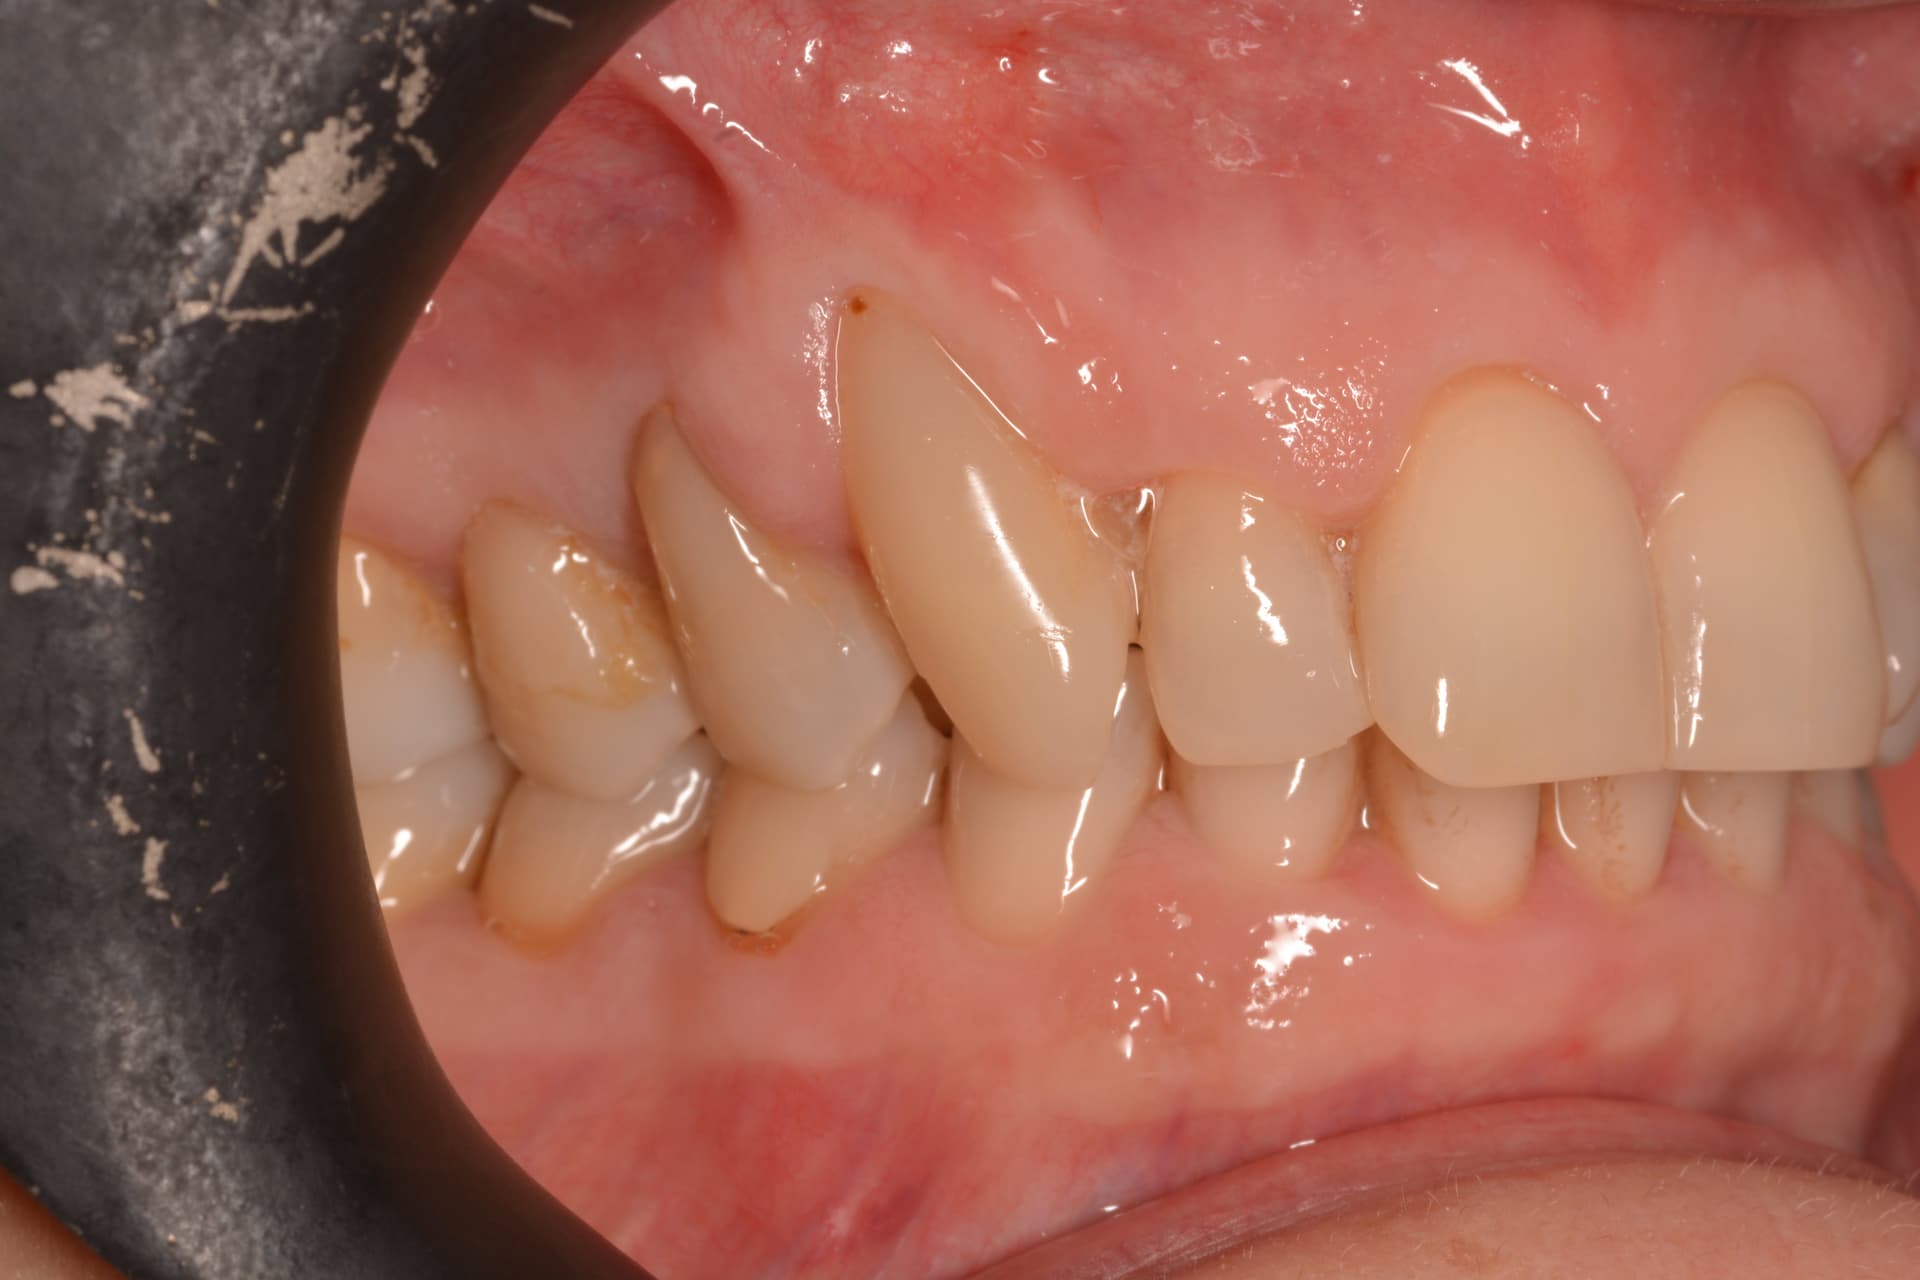

Injerto de tejido conectivo con técnica de túnel para cubrir recesiones radiculares